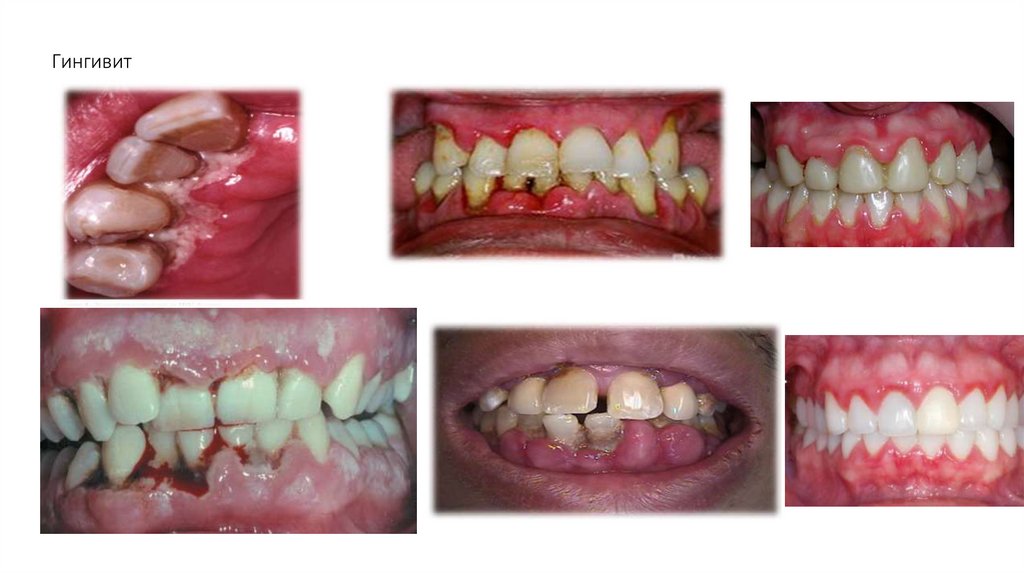

• Гингивит – воспаление десны (выше или ниже зубо-десневого прикрепления), обусловленное

неблагоприятным воздействием общих и местных факторов и протекающее без нарушения

целостности зубодесневого прикрепления.

• Формы: катаральный, гипертрофический, язвенный.

• Течение: острое, хроническое, обострившееся, ремиссия.

• Распространенность: локализованный, генерализованный.

22. Гингивит